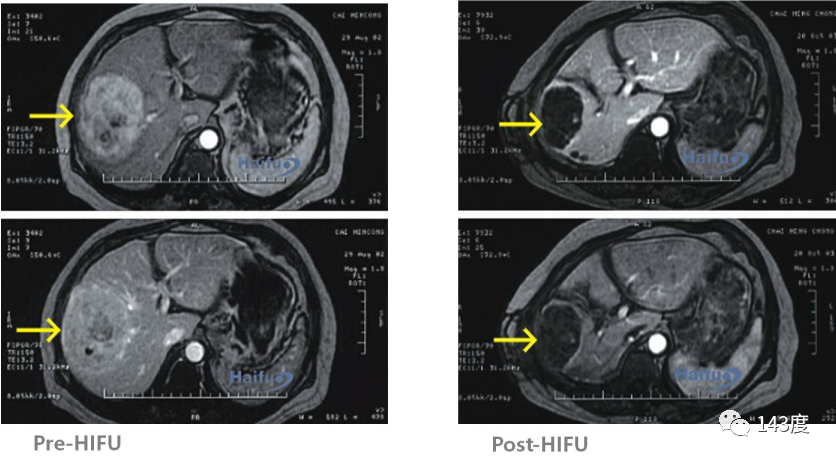

Liver Cancer Treatment Case 7:

Patient: Male, 62 years old, primary liver cancer

Lesion located next to the diaphragmatic roof, inferior vena cava, and portal vein system. After 5 sessions of radiofrequency and 2 sessions of TACE, residual tumor identified on follow-up MRI. HIFU treatment successfully inactivated the tumor while preserving the surrounding blood vessels.